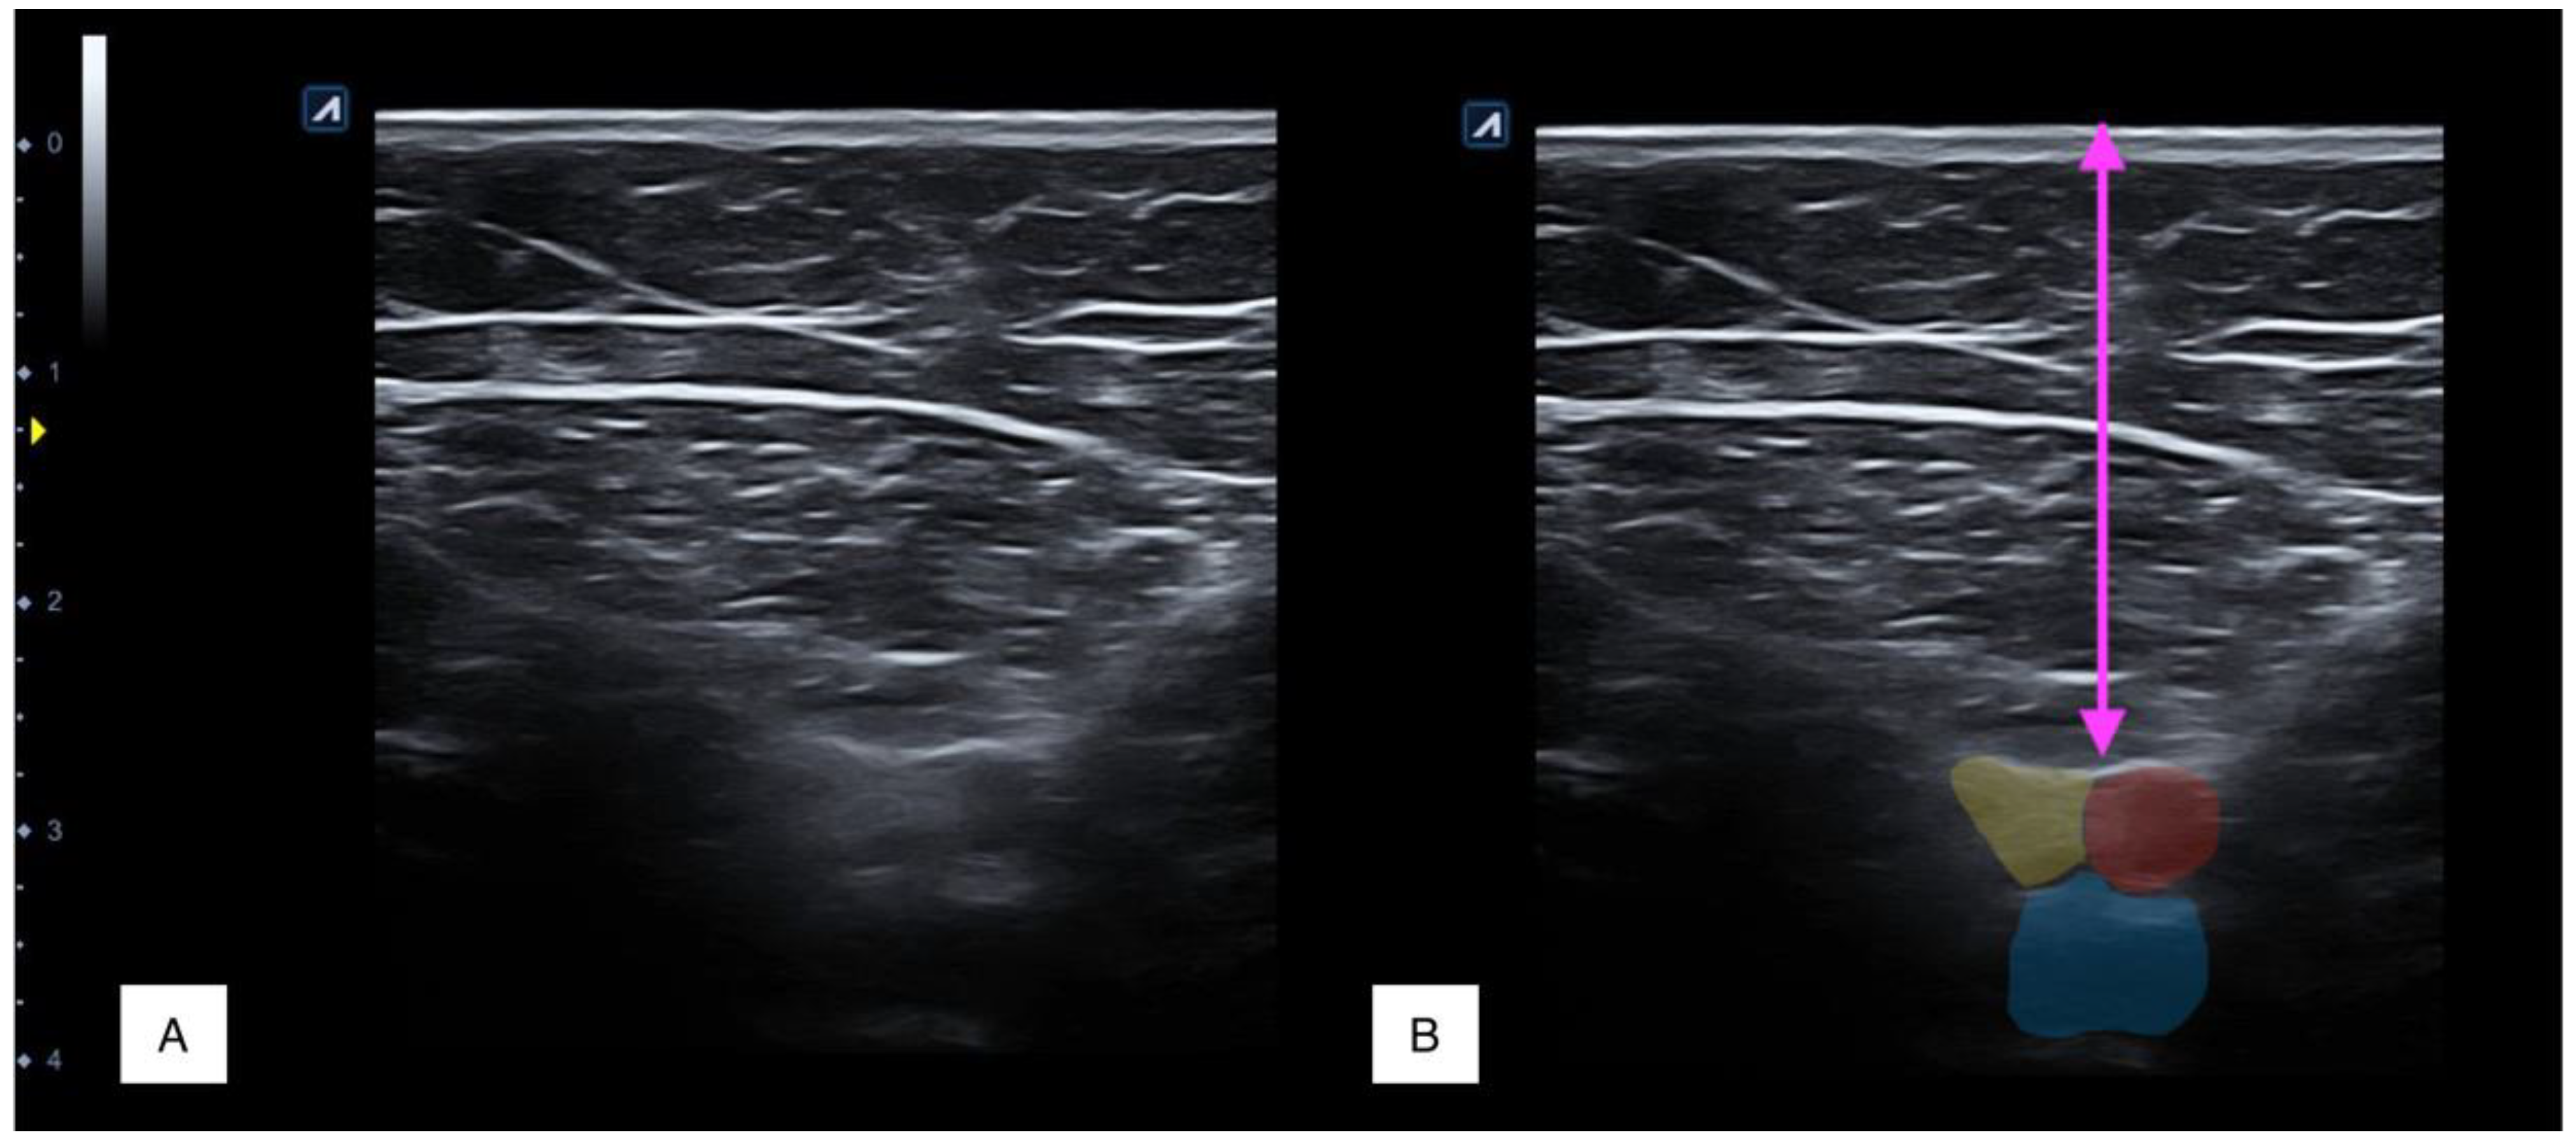

2.4. Procedure